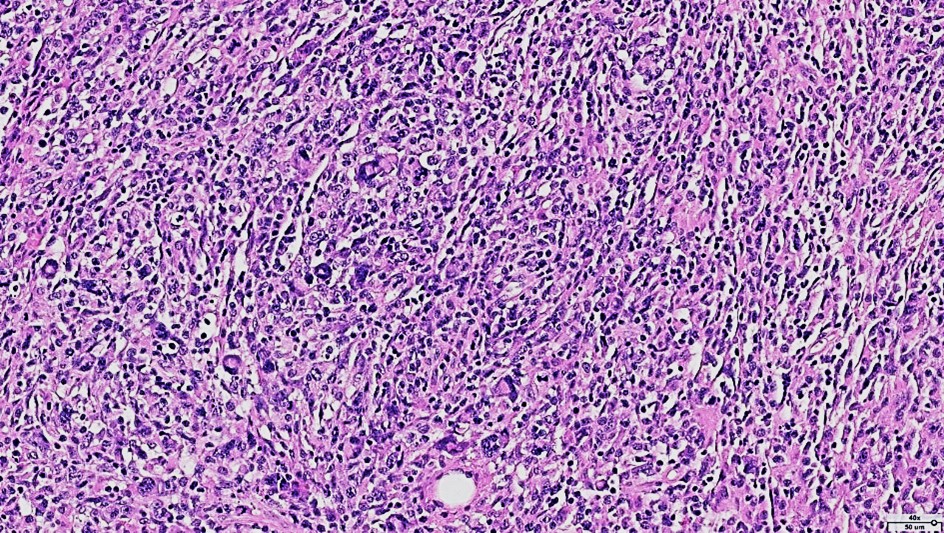

Histopathological examination revealed a non-circumscribed proliferation of large cells with marked nuclear pleomorphism, prominent nucleoli, and abundant clear cytoplasm, with numerous mitotic figures (Figure 3). Immunohistochemistry showed strong and diffuse expression of CD30 in atypical cells (Figure 4), and positivity for granzyme B, CD2, CD4, and CD25 in atypical T-cells (Figure 5). Numerous intermingled histiocytes were positive for CD68 and CD163, but negative in the atypical cells (Figures 6 and 7). ALK1 was negative in lymphoid cells (Figure 8). These findings supported the diagnosis of primary cutaneous anaplastic large cell lymphoma. Laboratory and PET-CT evaluation showed no extracutaneous disease. Localized electron beam radiotherapy was performed.

Figure 3: HE staining (40x): Proliferation of large cells with marked nuclear pleomorphism and mitotic figures.